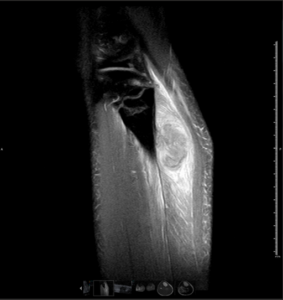

RM Pierna Derecha. Secuencia T2 Supresión grasa, corte sagital.